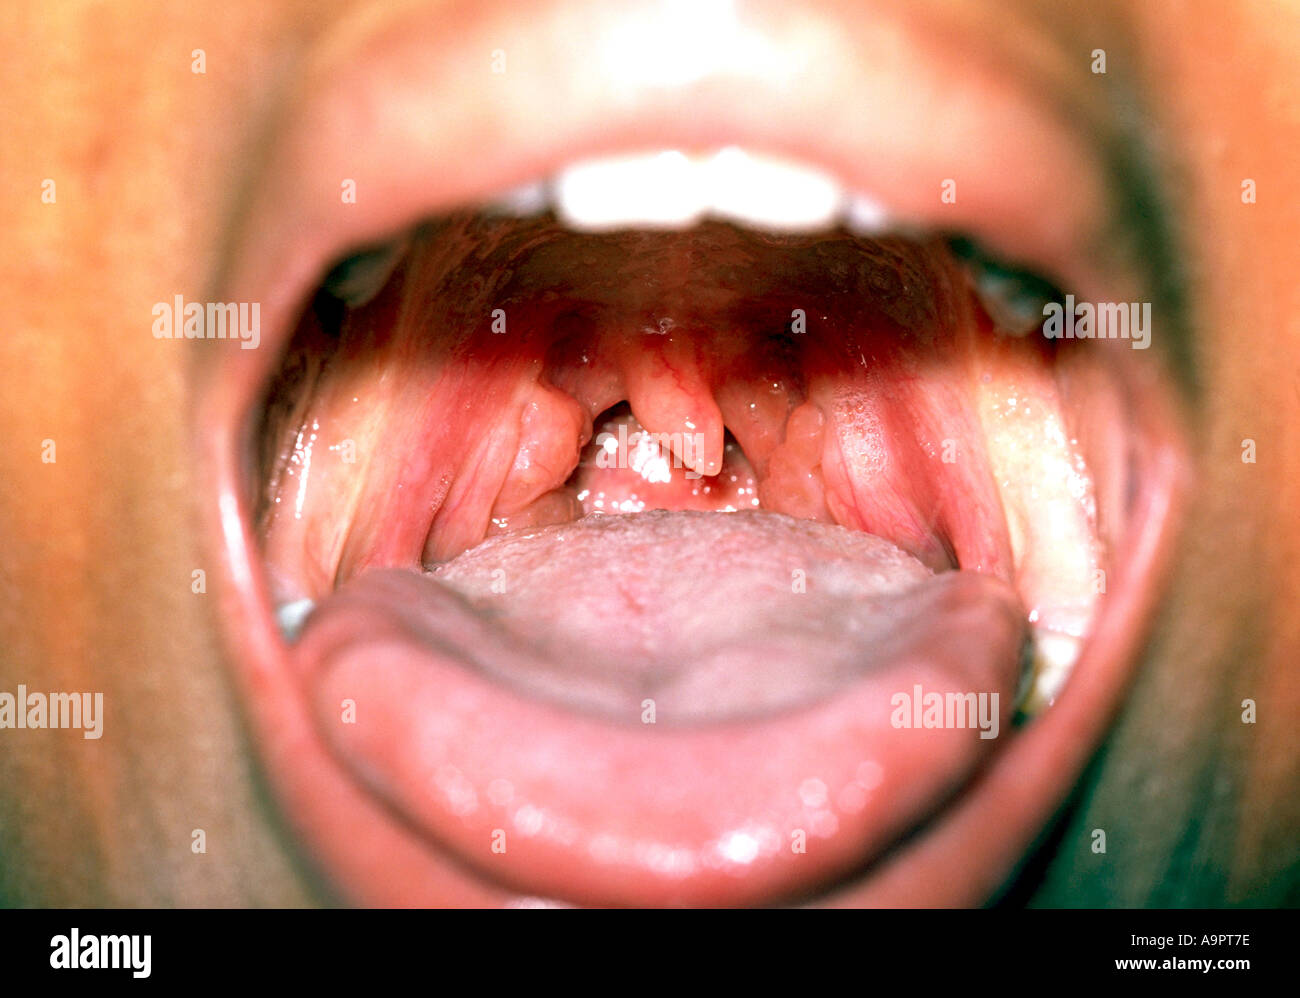

Vergrößerte Mandeln Stockfotohttps://www.alamy.de/image-license-details/?v=1https://www.alamy.de/vergrosserte-mandeln-image4055165.html

Vergrößerte Mandeln Stockfotohttps://www.alamy.de/image-license-details/?v=1https://www.alamy.de/vergrosserte-mandeln-image4055165.htmlRMA9PT7E–Vergrößerte Mandeln